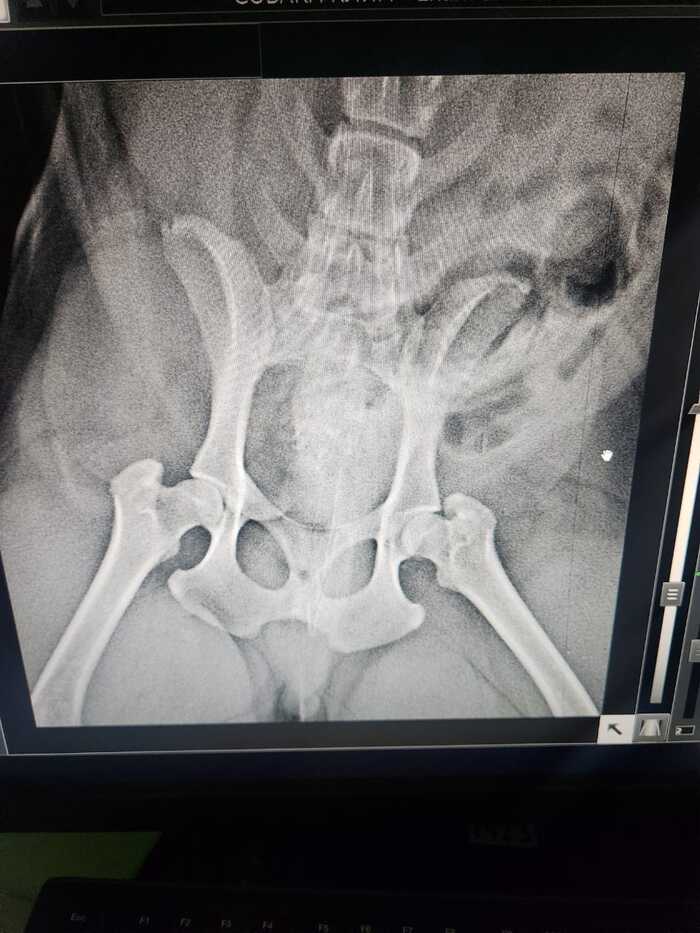

Сначала мы думали, что это почка. Врач прописал уколы кеторала, ношпы. Не помогло. Вот результат анализа крови, УЗИ и снимки с рентгена